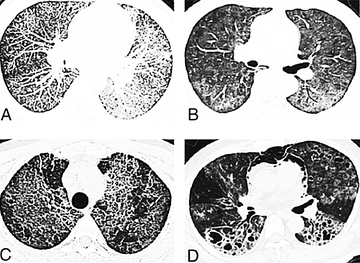

肺孢子菌肺炎临床主要表现为发热、干咳、进行性呼吸困难等,单纯吸氧不能缓解,经对因治疗后可迅速恢复。血常规、病原体检查、血清学检查、胸部X线、胸部CT等是该病的主要检查手段,病原体检查和血清学检查对确诊有重要意义,而胸部X线和胸部CT则对病情进行判断。治疗上除吸氧、维持水和电解质平衡等对症支持治疗以外,病原治疗是关键,首选药物为甲氧苄啶-磺胺甲基异噁唑(SMZ-TMP);对中-重度患者,在抗PCP治疗的同时或诊断72小时内使用肾上腺皮质激素艾滋病患者尽早进行高效抗反转录病毒治疗(HAART)。[2]